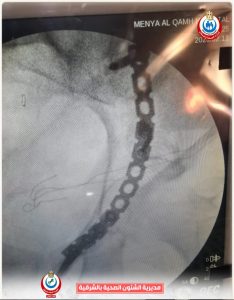

أوضح وكيل وزارة الصحة بالشرقية أن مستشفى منيا القمح المركزي استقبلت رجل يبلغ من العمر ٥٩ عاماً تعرض لحادث سير، يعاني من كسور معقدة بالحوض وكدمات متفرقة بالجسم، حيث تم التعامل الفوري مع الحالة وإجراء كافة الفحوصات الطبية والأشعات اللازمة لها، وحجزها بقسم الرعاية المركزة تحت إشراف أطباء الرعاية بقيادة الدكتور محمد رزق مدير الرعاية المركزة، مع وضع خطة علاجية عاجلة لتحقيق الاستقرار الطبي قبل العملية الجراحية.

أضاف الأستاذ محمود عبدالفتاح مدير الإعلام والعلاقات العامة بالمديرية، أن العملية الجراحية التي استغرقت ٣ ساعات تمت بواسطة فريق قسم العظام، بقيادة الدكتور محمد راشد استشاري جراحة الحوض، والدكتور أحمد عبدالسلام استشاري جراحة العظام، والدكتور سامح سمير رئيس قسم العظام، والدكتور عبدالرحمن محمد أخصائي العظام، والدكتور عبدالرحمن شلبي رئيس قسم التخدير، وبمشاركة تمريض العمليات الأستاذة هانم محمد، والأستاذة منى عيد، إلى جانب الفنيين والتمريض والعمال.

وأشار إلى أن الجراحة تم خلالها التعامل بدقة عالية مع الكسور المعقدة، بفضل الله بنجاح، وخرج المريض من غرفة العمليات في حالة مستقرة، وتم نقله إلى الرعاية المركزة لاستكمال المتابعة، وبعد ٢٤ ساعة تحسنت حالته وانتقل إلى قسم العظام الداخلي تحت متابعة طبية من أطباء المستشفى، وهو الآن بحالة جيدة.